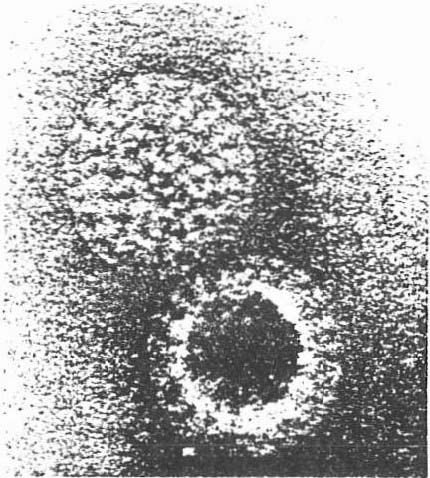

Sur une autre diapositive nous voyons le virus de la grippe (fig. 4). Il est très polymorphe et revêt des formes sphériques, allongées, filamenteuses. On distingue une enveloppe.

Fig. 4.